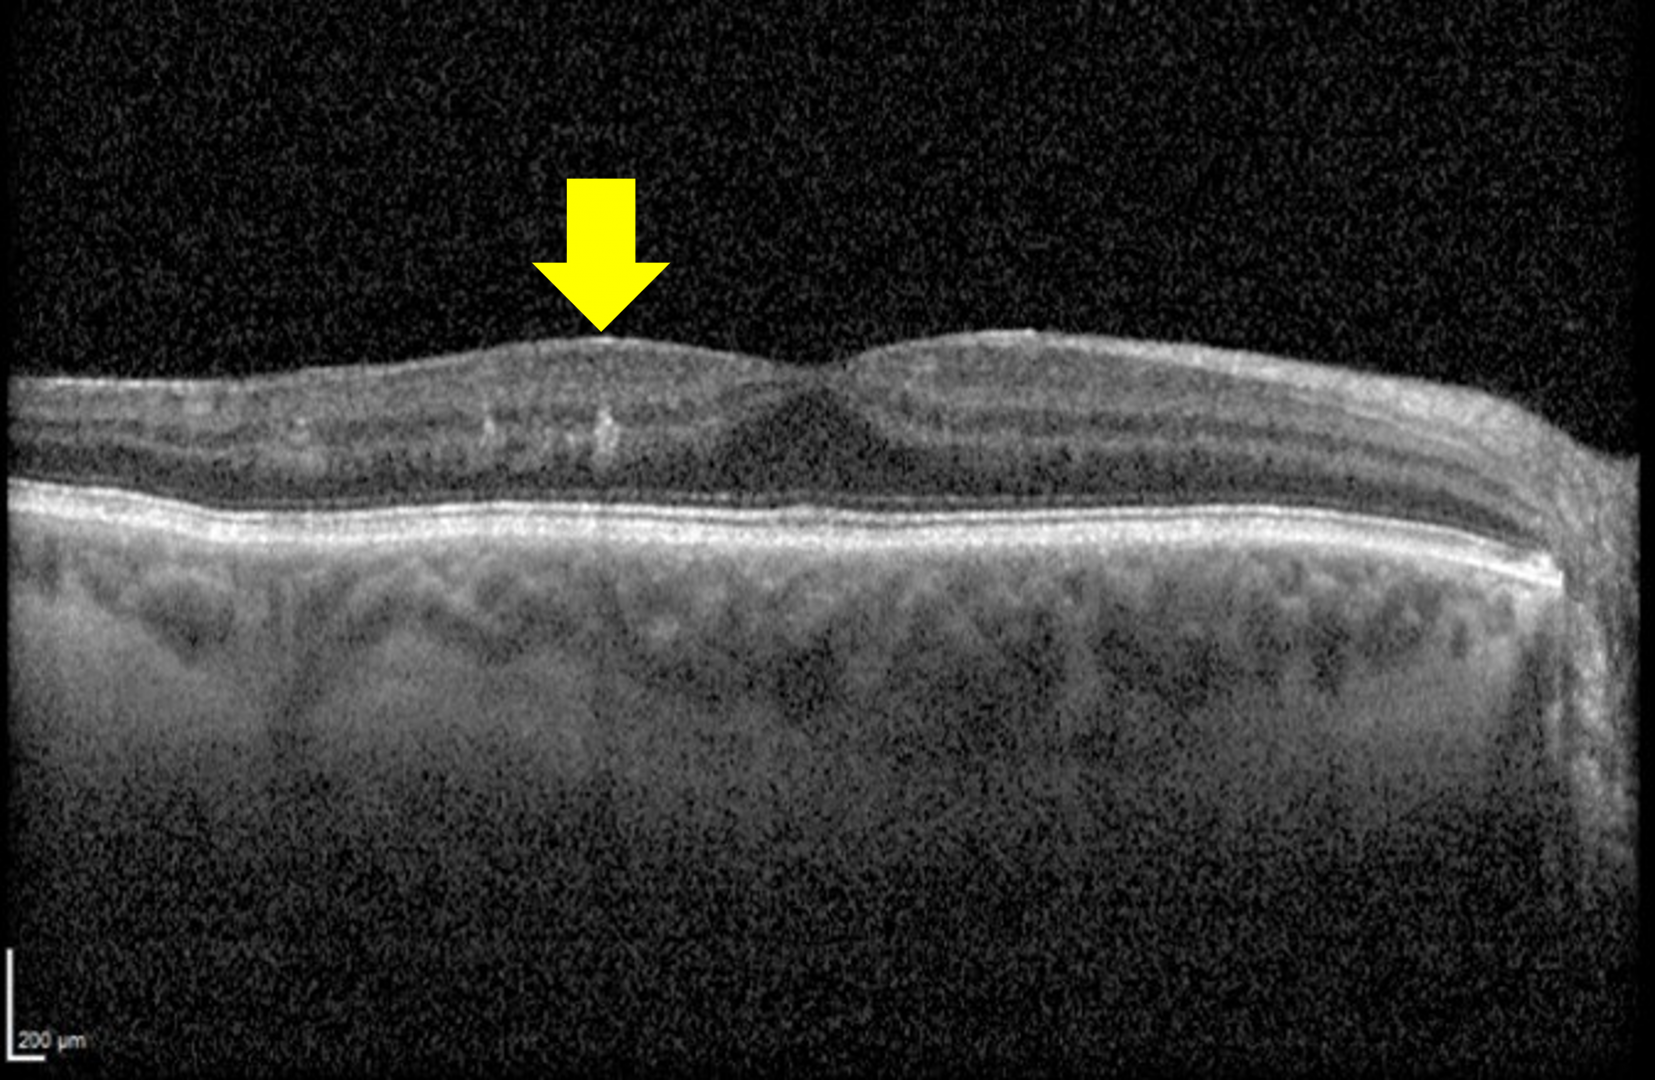

Recent studies have identified a clinical finding termed DRIL (disorganization of the retinal inner layers), which is used to describe poorly-defined boundaries of key inner retinal structures including the ganglion cell layer-inner plexiform layer (GCL-IPL) complex, inner nuclear layer (INL), and outer plexiform layer (OPL).

DRIL affecting more than 50% of the central 1-mm area of the retina is considered clinically significant. DRIL typically occurs in the central subfield of the ETDRS grid, and studies have shown that a 300 µm increase in DRIL is associated with a 1-line reduction in acuity.

The presence of DRIL has high diagnostic accuracy for identifying areas of non-perfusion (sensitivity 84.4%, specificity 100%). It is important to note however that not all areas of non-perfusion show signs of DRIL.